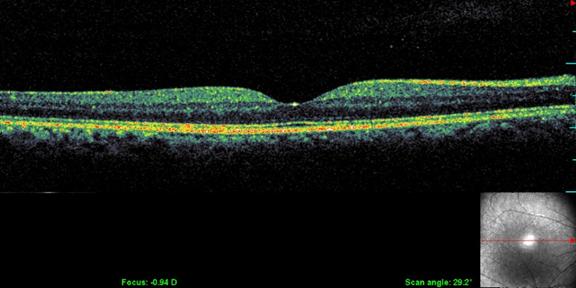

Optical Coherence Tomography (OCT)

OCT is a non-radiation mode of scanning that utilizes certain light waves for the scan.

OCT can show the retinal layers almost as if in biopsy (layer by layer). The resolution of the Spectral OCT scan available in MEH is 5 microns. Such highly precise scans help your doctor diagnose your AMD quite effortlessly.

• leading eye hospital for AMD treatment

Normal OCT

• top eye hospital for AMD

OCT in AMD

• best eye hospital for macular degeneration in Kerala

OCT is the most sensitive scan for monitoring the progress of AMD as well as for assessing the response to treatment.